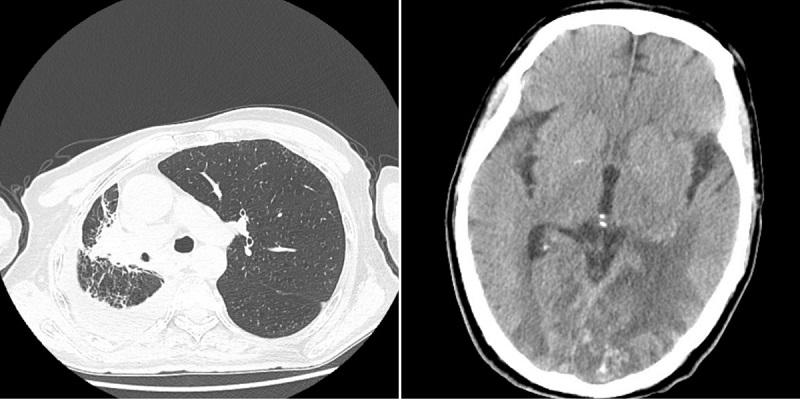

·2020年3月26日,李先生出现头晕症,检查发现脑部出现病灶,侯主任又为李先生行脑转移瘤射波刀治疗(3f)。

·2021年3月16日,李先生返院复查,检查结果提示:右肺肿瘤明显缩小,且李先生病情稳定。建议李先生继续服用中药并可回当地医院继续贝伐维持治疗。

从确诊到如今已过去7年,现在的李先生忙碌在生活、工作中,病情稳定,无不适感觉,也会遵照侯恩存主任的叮嘱定期到院复查。